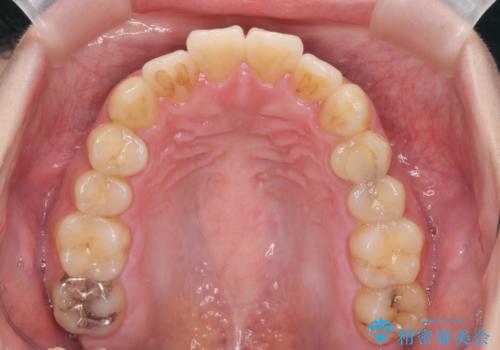

歯を抜かずに行う前歯の角度の改善

- 歯を抜かずに前歯の角度を改善したい、と矯正治療を希望され来院されました。

可及的に前歯部にIPR(歯間の削合)を行い、抜歯をせずマウスピース矯正システムインビザラインで歯の排列を行っていく治療計画としました。

治療の前後を比べると、がたつきや歯の角度が改善したことがしっかりと確認されました。